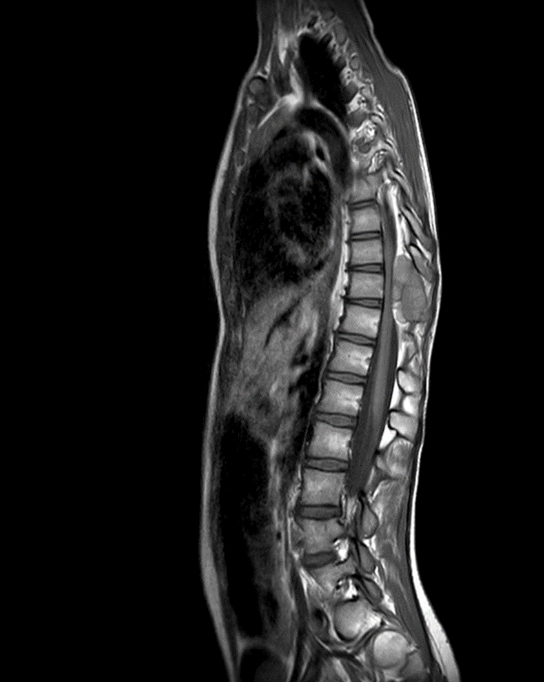

Ingrid è una bambina di 10 anni che viene in ambulatorio per un mal di schiena che dura da due settimane. Il dolore non è localizzato in un punto preciso, ma è diffuso al rachide dorso-lombare, non è influenzato dall’attività fisica né dal riposo, migliora con i FANS e talvolta provoca risvegli notturni (... sarà un tumore?). Per il resto Ingrid è sempre stata apiretica, ha un’anamnesi negativa per traumi, non ha avuto un calo di peso né una riduzione dell’appetito, ha un alvo regolare. All’esame obiettivo è presente una scoliosi dorsale sinistro-convessa, una limitazione della flessione anteriore del rachide e una dolorabilità alla percussione delle apofisi spinose dorso-lombari. La restante obiettività è negativa. Gli esami ematici eseguiti sette giorni prima erano risultati nella norma, in particolare indici di flogosi negativi (VES 2 mm/h, PCR 0,04 mg/dl), emocromo con formula leucocitaria nella norma, LDH inferiore ai limiti della norma (188 U/l). Vengono richieste una radiografia del torace e un’ecografia addominale, entrambe risultate negative. Dopo dieci giorni Ingrid torna in ambulatorio: stavolta zoppica e non riesce a stare in piedi. Il dolore è diventato sempre più intenso ed è resistente agli antidolorifici. Ingrid non evacua da quattro giorni, e da due giorni avverte dei formicolii ai piedi. A questo punto viene richiesta una RM in urgenza, che mostra una lesione di 4 x 5 cm localizzata al rachide dorsale, compatibile con una cisti ossea aneurismatica (Figura 1). Ingrid viene quindi inviata presso una Unità Spinale, dove esegue un intervento di laminectomia per l’asportazione completa della lesione e l’esame istologico, che mostra un quadro compatibile con cisti aneurismatica ossea.

La cisti ossea aneurismatica è un tumore osseo benigno, causa dell’1% di tutti i tumori primitivi ossei. È più frequente nel sesso femminile e si presenta in genere in giovani con meno di 20 anni. Pur avendo delle caratteristiche istologiche benigne è un tumore altamente aggressivo localmente, con un comportamento che, per la sua rapida crescita e il suo aspetto radiologico, può mimare quello dell’osteosarcoma. Si associa alla mutazione del gene USP6. Se la resezione è completa, come in questo caso, non c’è necessità di follow-up, mentre di fronte a una resezione incompleta il rischio di ricorrenza è del 20-30%. Ingrid ha iniziato un programma di riabilitazione graduale e tra 3 mesi eseguirà RM di controllo.